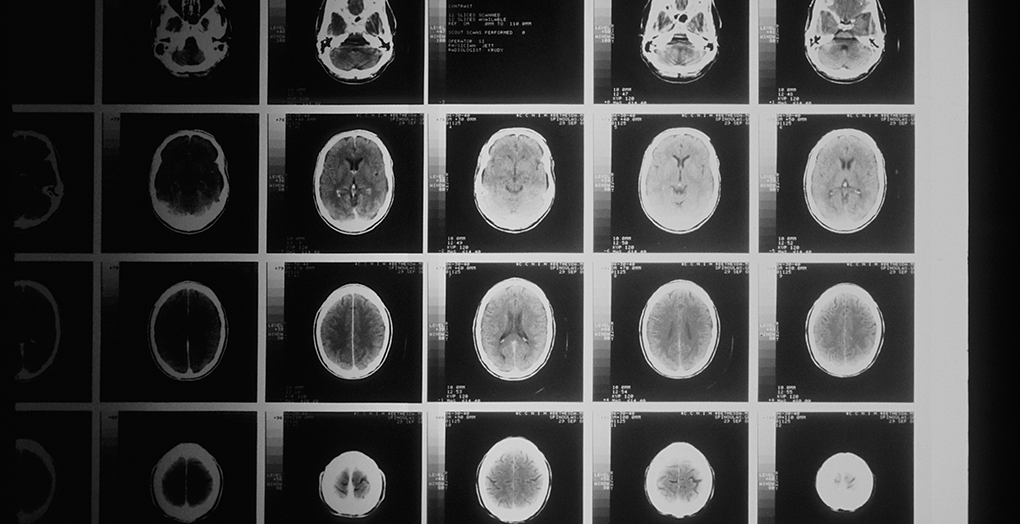

My first Magnetic Resonance Imaging (MRI) scan was in November 2019 when after an eye exam, I was sent straight to a specialist clinic to get a brain MRI. I knew a little bit about what it might be like from a friend who has them done regularly, but I had never experienced one myself. I know some people find the machines claustrophobic, but I didn’t experience that myself. Everything was a bit overwhelming at the time, so I just focused on getting through it, but I sensed that things were a bit more serious when they injected some contrast dye during the MRI. The imaging team were quick to write up their report for me to take to the GP, and that’s how my brain tumor expedition began.

Images used in this story are free stock images, and not images supplied by the story author.